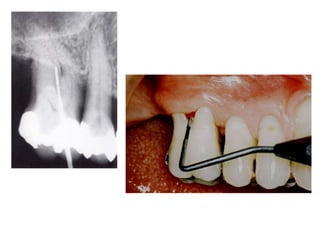

TRATAMENTO DAS LESÕES

ENDOPERIODONTAIS

Hemisseccção

DEL RIO, 1996